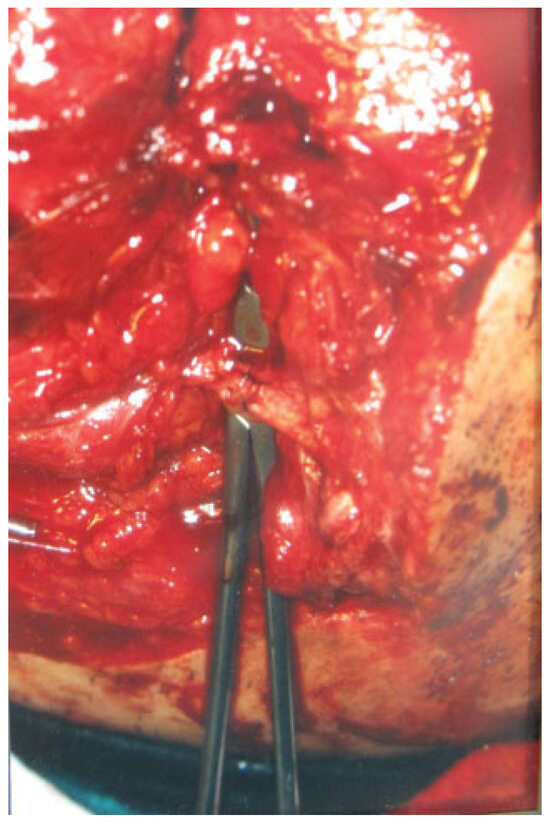

Figure 5. The transected stumps of the left parotid duct are identified and cannulated with a fine intravenous catheter.